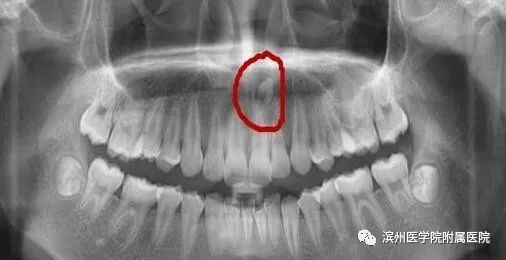

李奶奶的宝贝孙子6岁半了,上颌前面的两颗门牙已经替换了三个多月,可是两颗新牙间缝隙不见变小,反而越来越大了,远没有乳牙长得那么整齐。孙子门牙有大缝这事最近让李奶奶一直着急上火,平日总挂在脸上的笑容也不见了,今天一大早就带着孩子到滨州医学院附属医院儿童口腔科检查。儿童口腔科的医生经过专科查体并配合X线检查,发现是孩子的两颗新长门牙之间有一颗多生牙在作怪。

看完这些,大家对多生牙有所了解了吧,正如上面所讲,如果是在替牙期,多生牙的位置会阻碍正常新牙的萌出通道,导致对应恒牙的萌出位置发生异常,例如牙齿发生扭转、倾斜、拥挤或牙缝过大甚至不能萌出。而且,多生牙奇怪的外形也会严重影响小主人口腔美观及心理健康;也有可能导致含牙囊肿的发生,若无视它继续生长,骨质逐渐向周围膨胀,则会形成面部畸形。